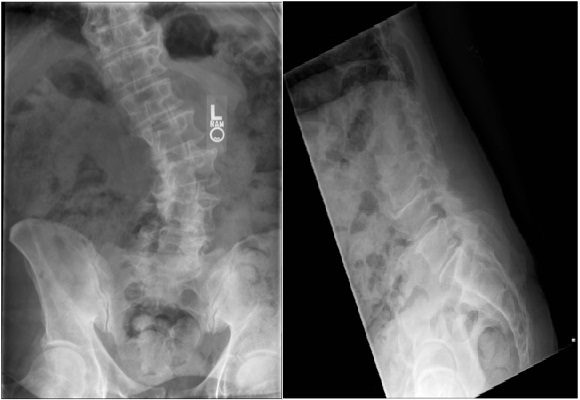

Flatback deformity is a condition of the spine in which the normal inward curve of the lower back (lumbar lordosis) is reduced. Patients with flatback deformity lean forward and have difficulty standing upright. This causes significant pain and fatigue in the back and legs.